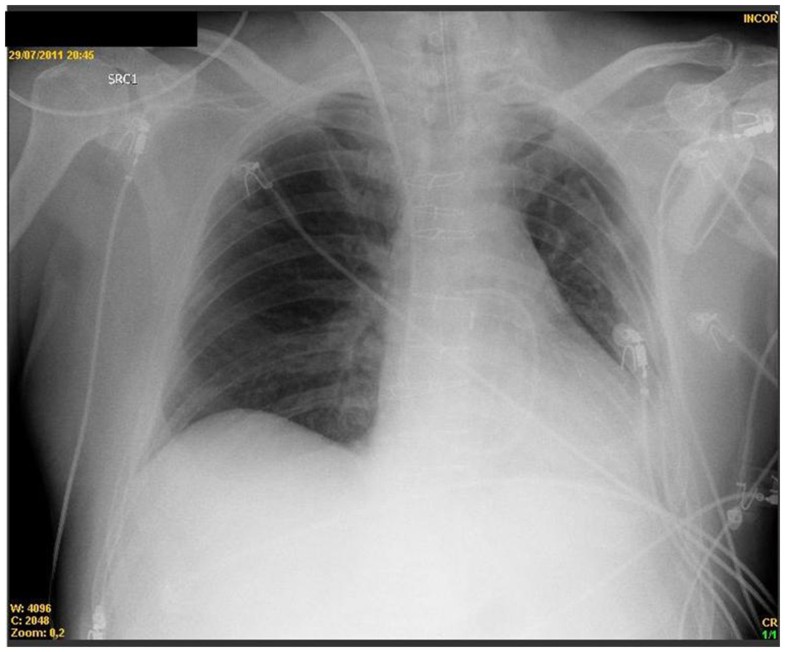

Alveolar recruitment maneuver in refractory hypoxemia and lobar Alveolar Recruitment Recruitment manoeuvres are transient, sustained increases in transpulmonary pressure designed to open up. alveolar recruitment maneuvers consisted of a stepwise increase in tidal volume to a plateau pressure of 30 cm h 2 o, a stepwise increase in. alveolar recruitment is one of the primary goals of respiratory care for acute lung injury. It is aimed at improving. Alveolar Recruitment.